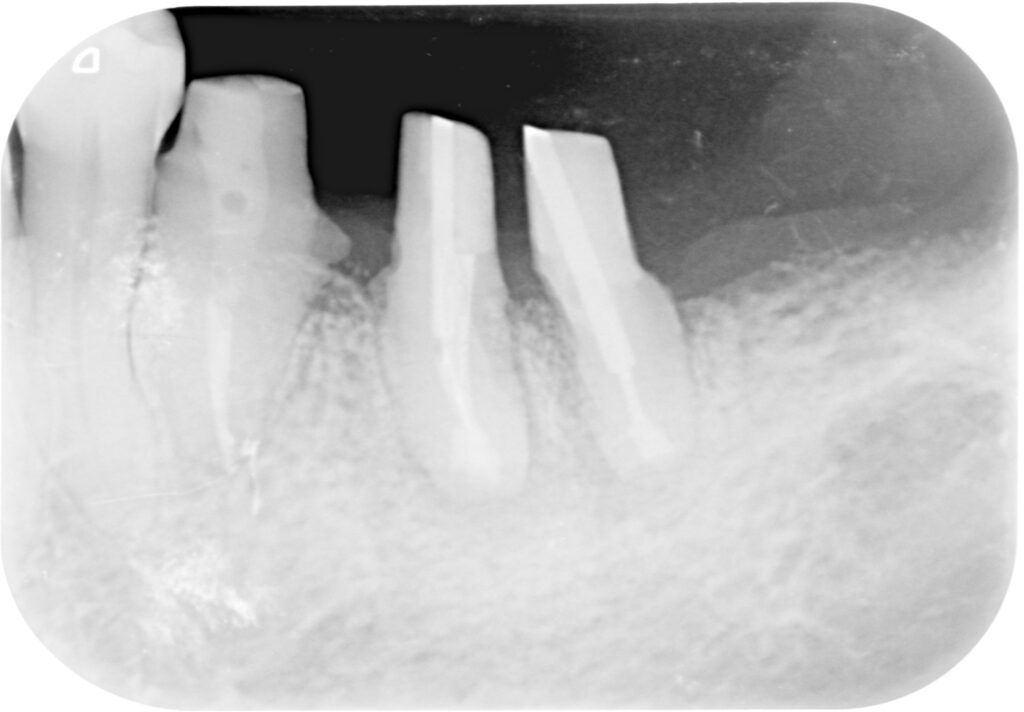

재신경치료는 치아의 뿌리까지 연결 통로를 관통시켜주는 것이 중요한데, 현재 상황에서 불가능하여 뿌리 끝의 염증을 제거하기 위해 의도적재식술을 시행하였습니다. 시행 중 치아 뿌리가 분리되면서 큰 어금니 한 개가 작은 어금니 두개로 분리되었습니다.

맨 뒤 사랑니는 제거한 상태입니다. 자연치를 살리기 위한 방법으로는 재근관치료, 치근단 절제술, 의도적재식술, 치근 분리술, 치관 확장술, 포스트&코어가 있는데요, 하나의 치아를 위해 상기 치료가 모두 적용되었습니다.

크라운 수복 후 촬영한 사진입니다. 의도적재식술은 치아를 뽑아 치아 뿌리에 염증 조직을 제거하고, 뿌리 끝을 충전재로 폐쇄시킨 뒤 다시 심는 수술입니다.